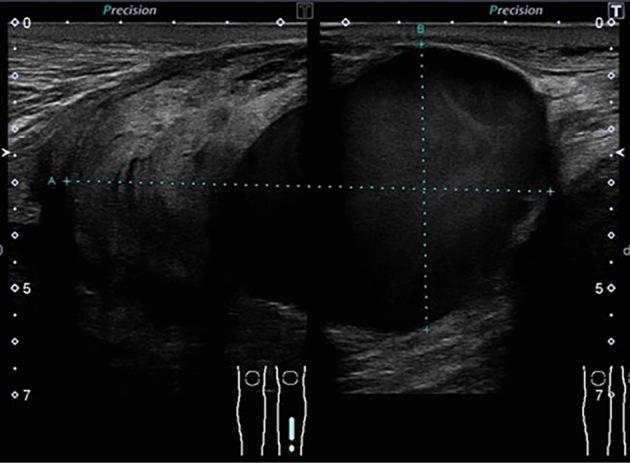

Giant Bilateral Anterior Tibial Pseudoaneurysms.

https://cdn.ncbi.nlm.nih.gov/pmc/blobs/0bef/9556228/679a6861cf98/1349-7235-61-2819-g001.jpg